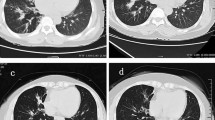

Mucus plugs were observed in the central bronchi on thoracic computed tomography (CT) in 22 patients (76%) treated with biologics: 17 of them were treated with mepolizumab and five with benralizumab. Improvement in mucus plugs after treatment was achieved in 18 (82%) patients, including 13 patients (76%) treated with mepolizumab and all patients (100%) treated with benralizumab. In the patients with an improvement of mucus plugs in the bronchi, there was a significantly larger reduction of peripheral blood eosinophil counts after anti-IL-5/IL-5Rα mAb treatment than in those without radiographical improvement (p < 0.001, Table 2), even when only the cases treated with mepolizumab were analyzed.

Our data demonstrated that anti-IL-5/IL-5Rα mAbs not only improved clinical control but also radiographic abnormalities, such as mucus plugs in the bronchi. It is often difficult to evaluate whether biologics improve ABPA-specific pathology or underlying asthmatic condition. In contrast, mucus plugs in the central bronchi, often accompanied by central bronchiectasis and high-attenuation mucus, are specific for ABPA39,40. Although mucus plugs are also present in the bronchi of severe asthma, they are located in the distal airways and are not accompanied by bronchiectasis or high-attenuation mucus41. In the present study, mucus plugs reduced in size or disappeared after treatment with anti-IL-5/IL-5Rα mAbs in 82% of patients, suggesting that these biologics directly affect the pathophysiology of ABPA. Crosslinking of cysteine thiol groups in mucin partially mediated by eosinophil peroxidase has been demonstrated to be important for the formation of mucus plugs in the asthmatic airways41, and possibly in the airways of ABPA. In addition, we previously demonstrated that A. fumigatus can induce the release of extracellular traps from eosinophils, which are abundant in the mucus plugs of patients with ABPA42. Extracellular traps from activated eosinophils, composed of nuclear chromatin, form denser and more stable aggregates than neutrophil-derived extracellular traps and are also present in the mucus plugs of other eosinophilic diseases, such as chronic rhinosinusitis with nasal polyps and eosinophilic otitis media43. These data suggest that IL-5 and eosinophils are indispensable for the formation and maintenance of mucus plugs in patients with ABPA.

In the present study, 20 patients initially received mepolizumab, and nine received benralizumab. The clinical effects of mepolizumab and benralizumab on ABPA with respect to the control of daily symptoms or exacerbations were equivalent. However, we found a substantial difference between these biologics in their effects on mucus plugs. Although not statistically significant, benralizumab treatment resulted in a higher rate of disappearance of mucus plugs than mepolizumab treatment. Furthermore, the patients with radiographical improvement on mucus plugs demonstrated significantly larger reduction rate of peripheral blood eosinophil counts. In addition, a switch therapy from mepolizumab to benralizumab diminished the residual mucus plugs on treatment with mepolizumab in four patients, including the two patients we had previously reported34. The potent effect of benralizumab in suppressing mucus plug maintenance in the airways is likely related to its robust ability to deplete eosinophils in peripheral blood and tissues. In refractory eosinophilic asthma, bronchial subepithelial eosinophil counts after one year of treatment with mepolizumab were not statistically different from those in the placebo treatment group44. In contrast, subcutaneous benralizumab significantly reduced the airway mucosal eosinophil counts, with no eosinophils observed in the mucosal and submucosal tissues at day 84 in the benralizumab group45. These differences in the effects of mepolizumab and benralizumab in reducing the airway eosinophil numbers may have resulted in the difference in their effect on ABPA mucus plugs. Removal of eosinophilic mucus plugs by strict management of airway eosinophils with benralizumab prevents airway destruction and improves the long-term prognosis of patients with ABPA.